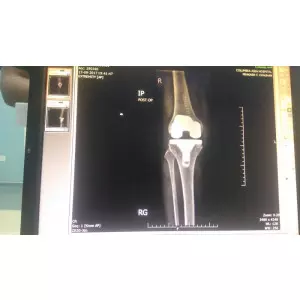

Jay Patel - USA